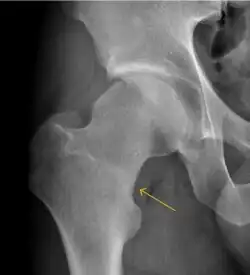

Synovial chondromatosis can be confidently diagnosed by X-ray when calcified cartilaginous chondromas are seen. However, other synovial proliferative processes, such as pigmented villonodular synovitis, require MRI for accurate diagnosis, although noncalcified synovitis can be suspected in radiographs by indirect signs, such as soft tissue swelling and/or erosions in the femoral head, femoral neck, or acetabulum (Figure 7).[1]

Radiological signs of transient osteoporosis of the hip include localized osteoporosis of the femoral head and neck (Figure 8). Nevertheless, final diagnosis has to be made with MRI to differentiate it from avascular necrosis and from insufficiency or stress fractures of the femoral head or neck. In case of AVN, radiographs can only demonstrate delayed or advanced signs. Staging according to Ficat classification ranges between normal appearance (stage I), slight increased density in the femoral head (stage II), subchondral collapse of the femoral head with or without “crescent” sign (stage III), and advanced collapse with secondary osteoarthritis (stage IV). In the case of stress or insufficiency fractures X-ray sensitivity has been proven to be much lower than MRI, which is currently the gold standard.[1]

Figure 8:

-

X-ray of a patient with transient osteoporosis of the left hip showing osteoporosis.[1] -

Coronal stir imaging in transient osteoporosis, showing diffuse edema.[1] -

Scintigraphy (A), sagittal T1 (B), and coronal PD fat sat of a patient with a subchondral fracture of the femoral head with convex shape to the articular surface.[1] -

Coronal T1 of a patient with avascular necrosis of the femoral head.[1]